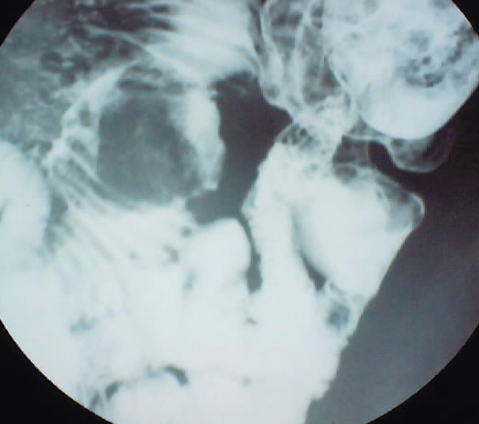

Nishit Patel, MD; Greg Dupuis, MD; Robert Wild, MD, PhD, MPH

A 17-year-old girl with a recently discovered ovarian cyst was referred to the emergency department (ED) by her primary care provider.